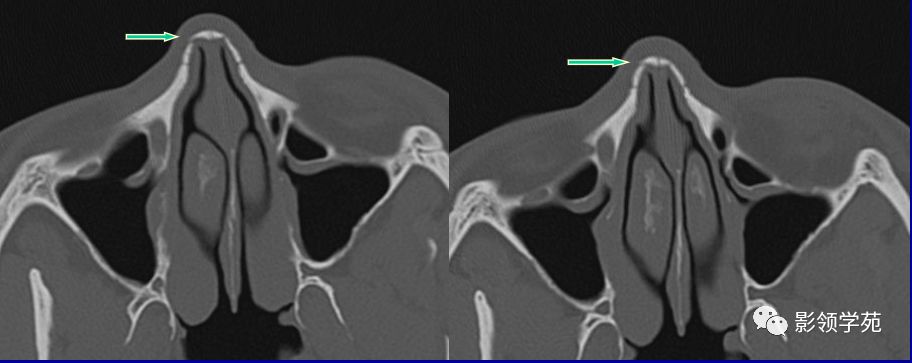

鼻颌缝

鼻额缝

额颌缝

鼻骨间缝

鼻骨孔

缝间骨